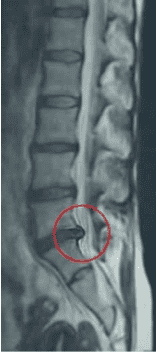

Przykład